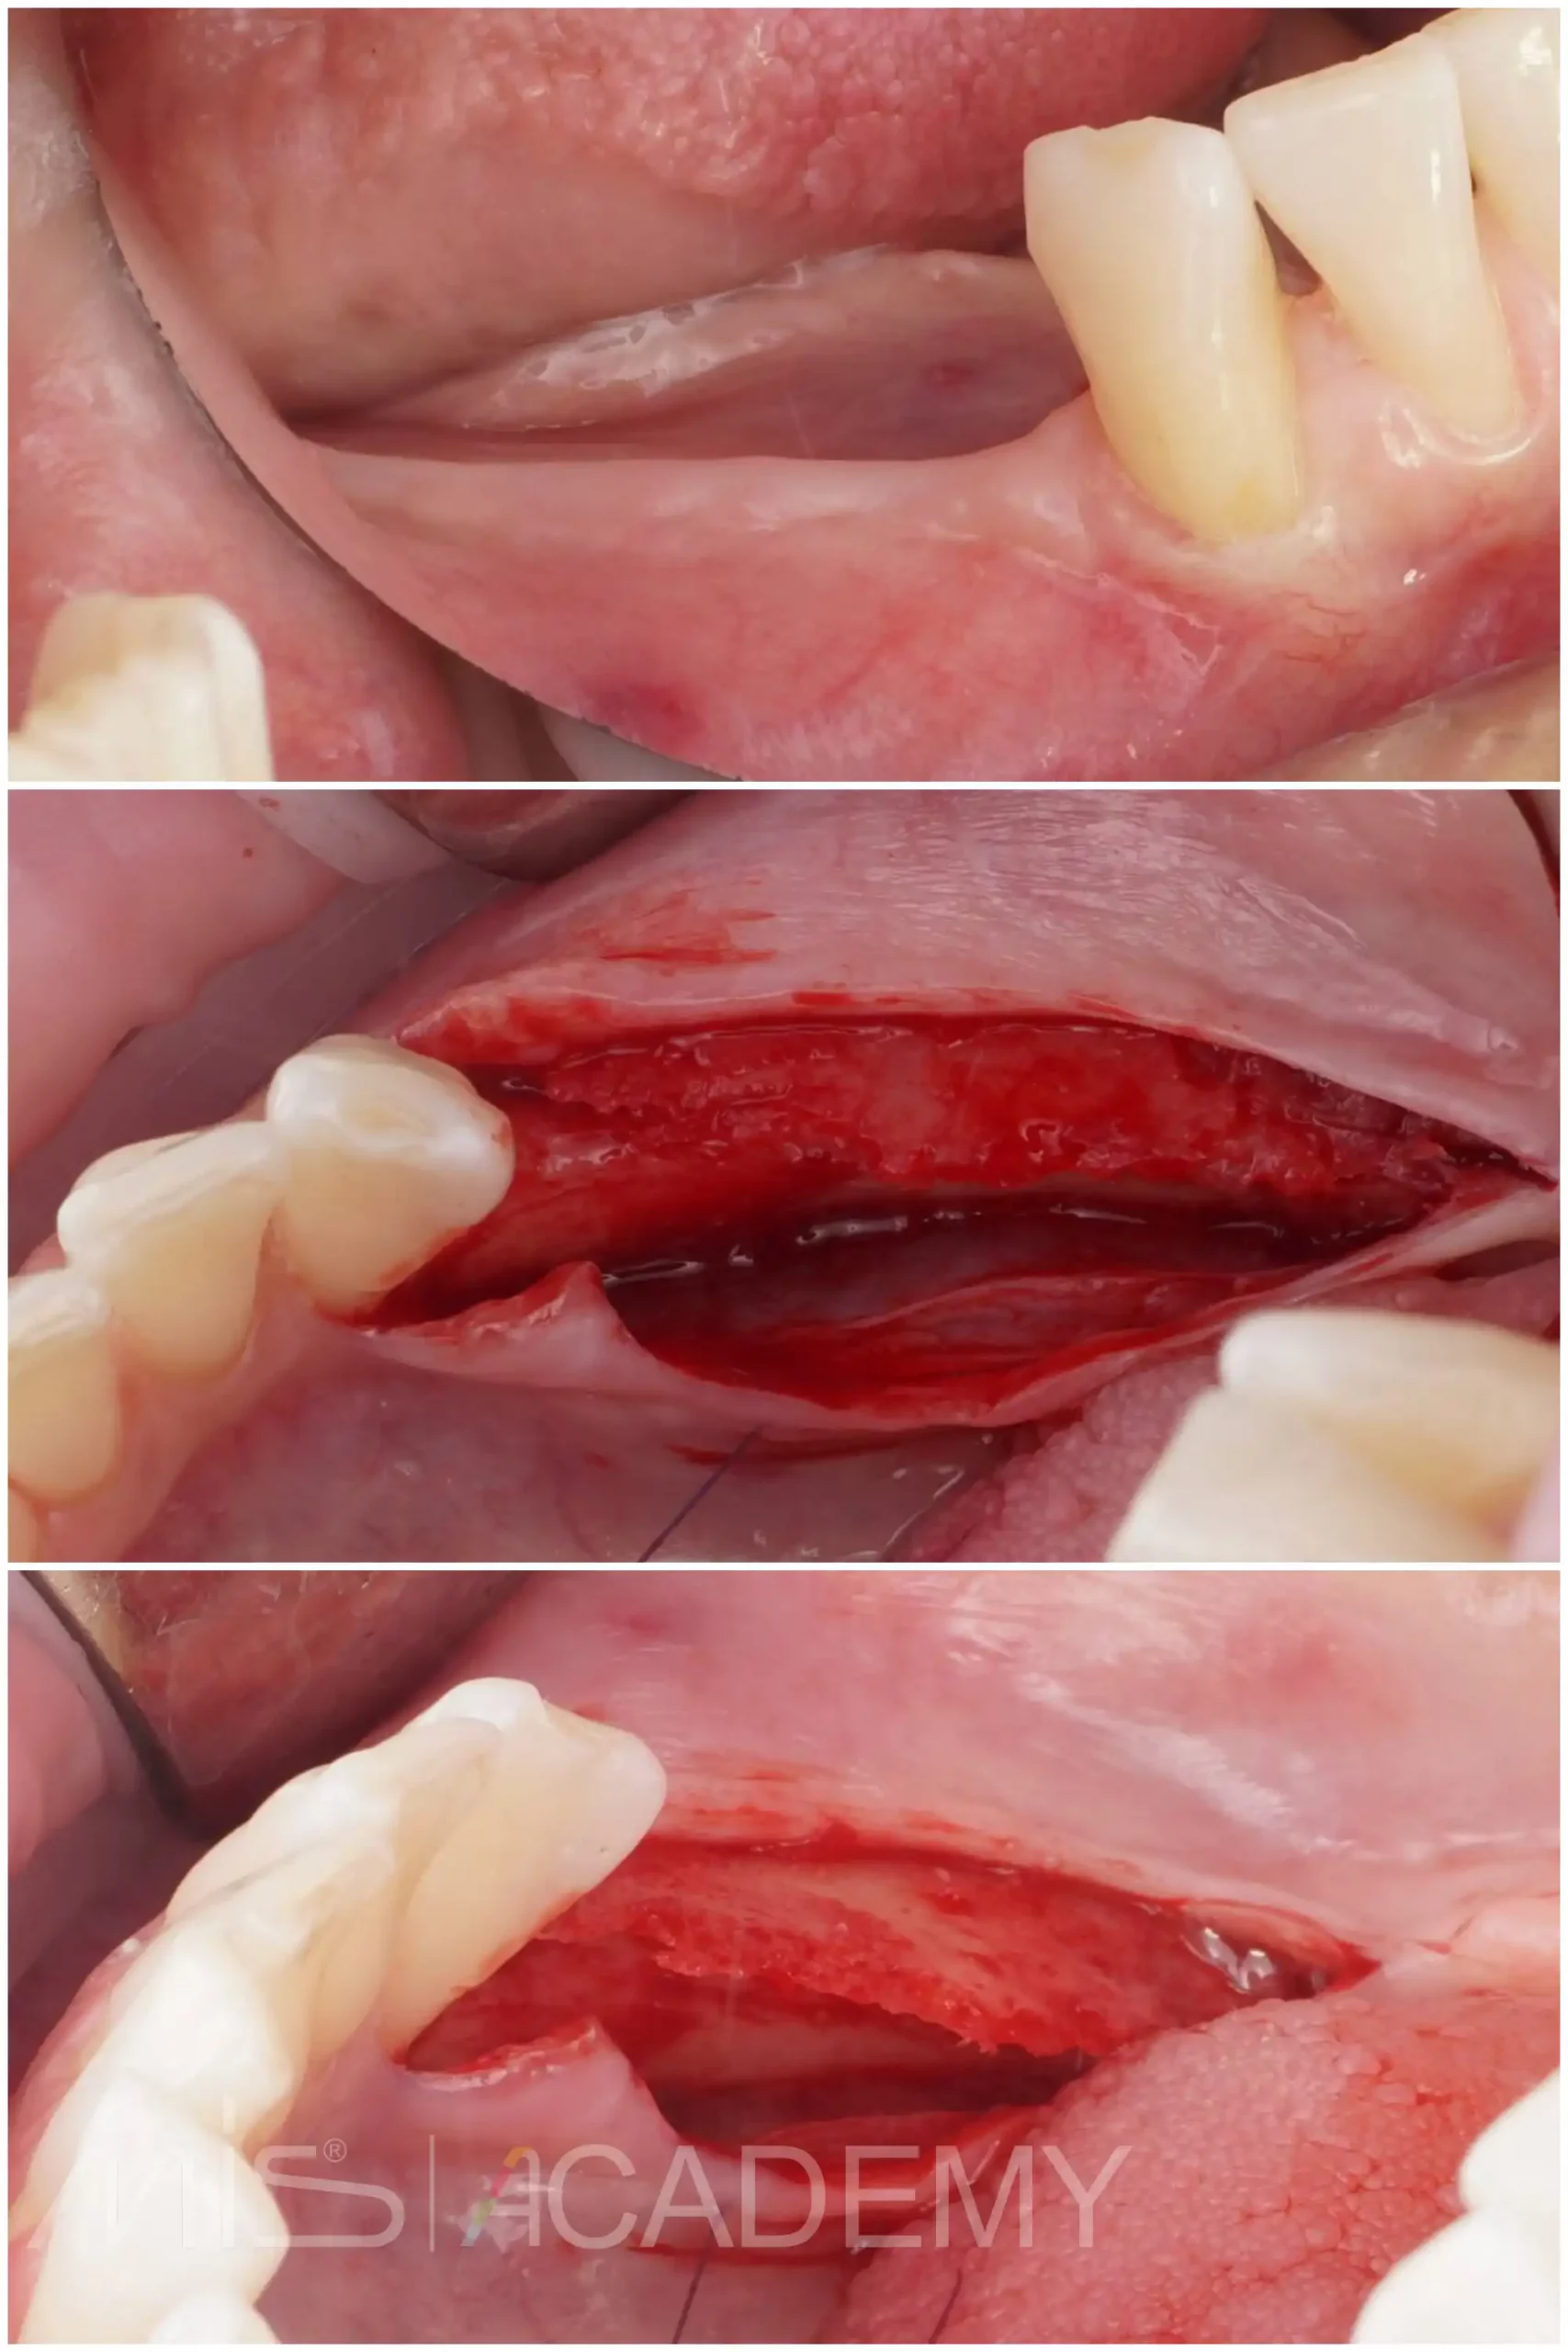

Восстановление дефекта на нижней челюсти:

— Gen-os.

— Ауто и ксено Lamina curved, которая была зафиксирована надкостничными швами.

— Раскрытие через 6 месяцев. Ламина до конца не резорбировалась, аккуратно без проблем удаляем, под ней был миллиметровый фиброз, под которым плотный фундамент. Фиброз не удаляю, чуть отодвигаю в зоне где будет имплантация, дою дозреть и использую его для фиксации ССТ с бугра.

— Снятие швов через 2 недели.